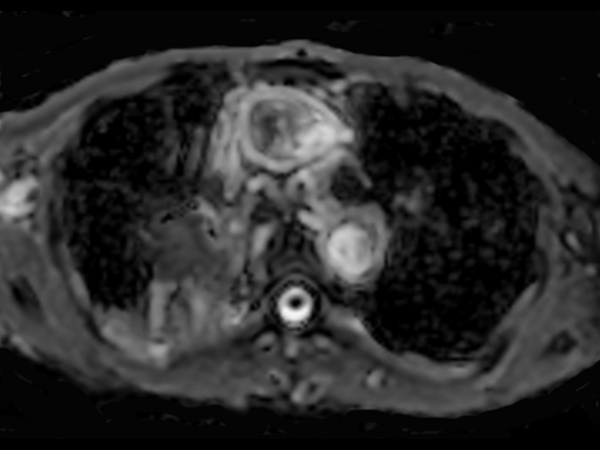

Patient with lung cancer. The ExamCard includes techniques for efficient fat-free imaging over large field-of-views (mDIXON XD), a diffusion procedure with less distortion (DWI TSE XD), a multi-phase contrast-enhanced sequence (4D FreeBreathing) to improve imaging confidence and Compressed SENSE to accelerate the entire exam.

DWI TSE XD b1000 Compressed SENSE

DWI TSE XD b1000 (ADC) Compressed SENSE